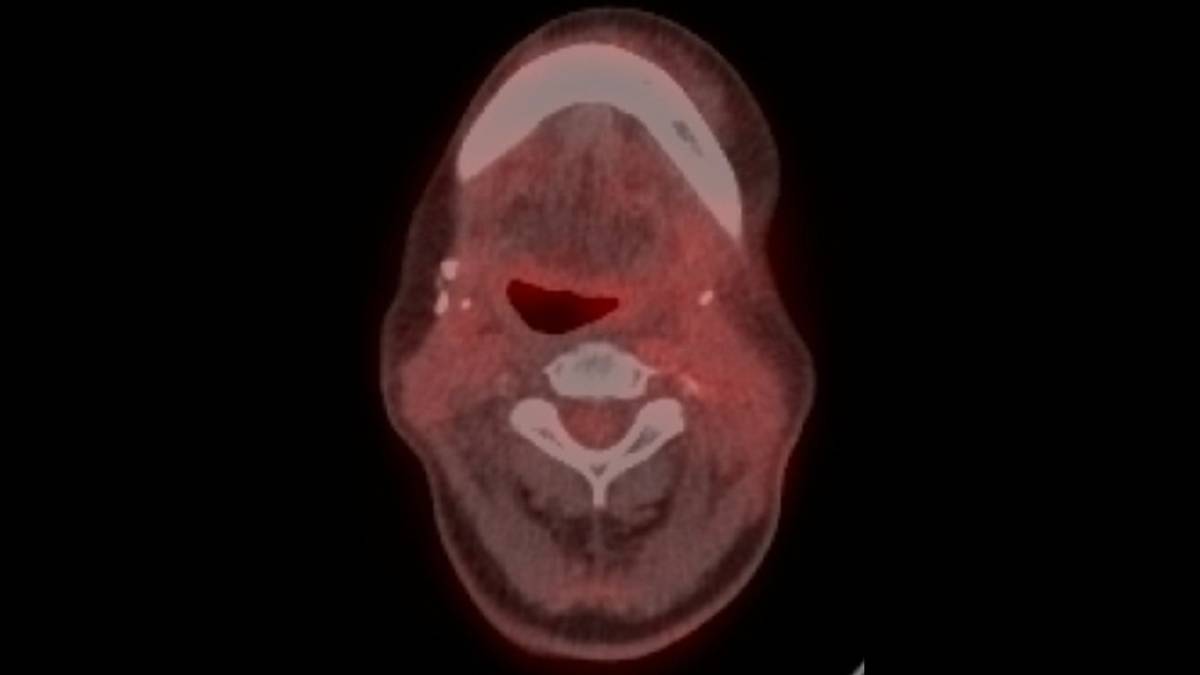

沒有標靶藥物抗藥性,後續免疫療法成效較佳。頭頸癌患者的正子攝影,可以見到沒有黃色亮部的腫瘤顯影。(陽明交大提供)